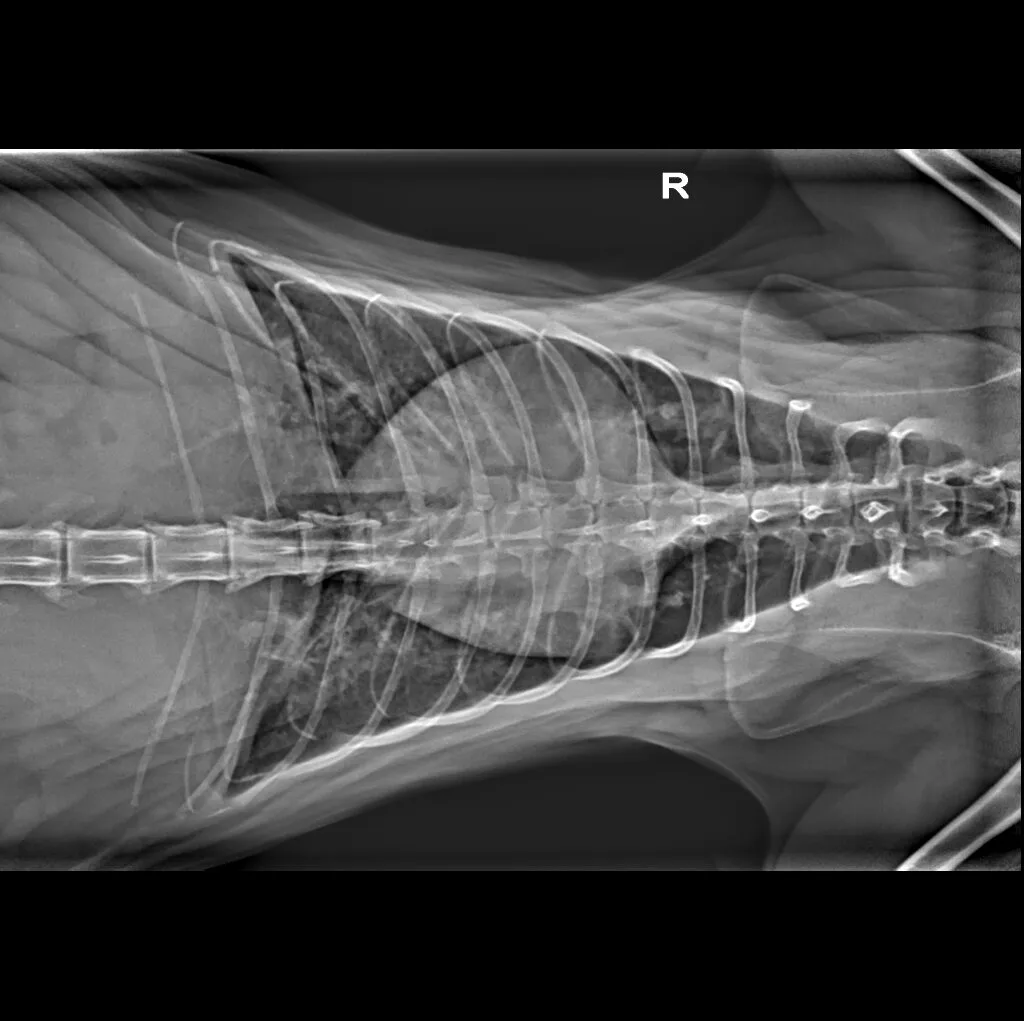

At Grand Ave. Pet Hospital, we utilize digital radiography to diagnose and monitor a wide range of medical conditions in pets. Digital X-rays provide clearer images, faster results, and safer radiation levels, ensuring the best possible care for your furry companion.

Digital radiography offers superior imaging quality and precision compared to traditional X-ray techniques. It allows us to detect hidden health issues early, leading to faster and more effective treatments.

🔹 Cardiac & Respiratory Conditions – Evaluating heart disease and lung disorders